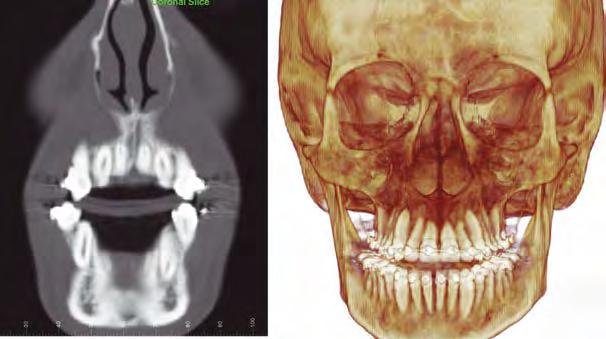

–Tratamiento de un caso de Ortodoncia y Cirugía Ortognática con placas preformadas y tecnología 3D, por la Dra. Elena Bonilla Morente y cols. [62]

–Uso del anclaje esqueletal como alternativa eficiente en el manejo ortopédico de clases III por deficiencia de maxilar superior, por el Dr. Carlos Becerra y cols. [74]

–MARPE, una alternativa a la disyunción en el paciente adulto, por el Dr. Enrique Solano y cols. [88]